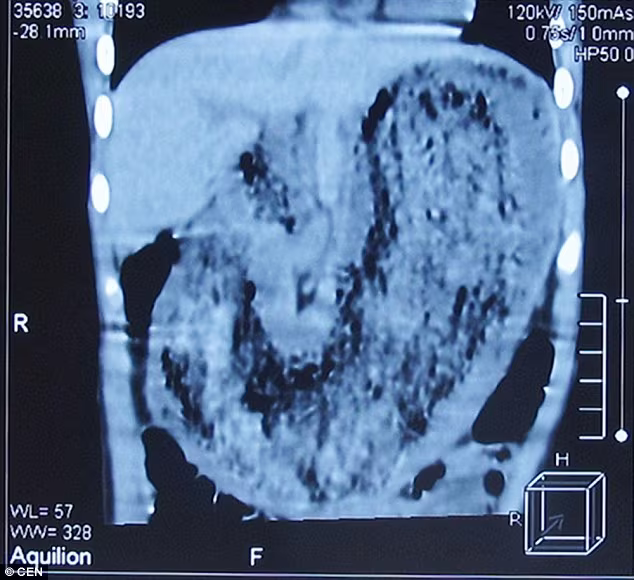

Cha mẹ bé đã đưa đến một bệnh viện địa phương để điều trị. Sau khi kiểm tra sức khỏe thông qua chụp CT, các bác sĩ đã phát hiện ra một “vật thể lạ lớn” trong dạ dày cô bé, tuy nhiên họ cũng không biết chắc chắn đó là khối chất gì.

Phẫu thuật lấy búi tóc nặng 2kg ra khỏi dạ dày bé gái ảnh 1Hình ảnh búi tóc trong dạ dày qua hình ảnh chụp CT

Bé gái tiểu học mau chóng được chuyển lên bệnh viện cấp tỉnh và các bác sĩ chuẩn đoán khối chất trong dạ dày là tóc, móng tay và vải quần áo kết chặt thành một búi. Tiến sĩ Zhang Shufeng chuyên về nhi khoa, người phẫu thuật cho bé gái, đã lấy ra một búi tóc khổng lồ nặng đến gần 2kg.